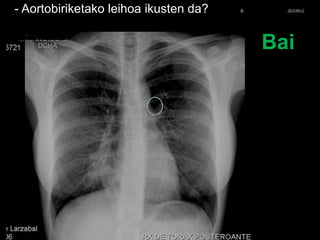

- Aortobiriketako leihoa ikusten da?

Bai